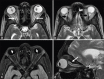

Figures